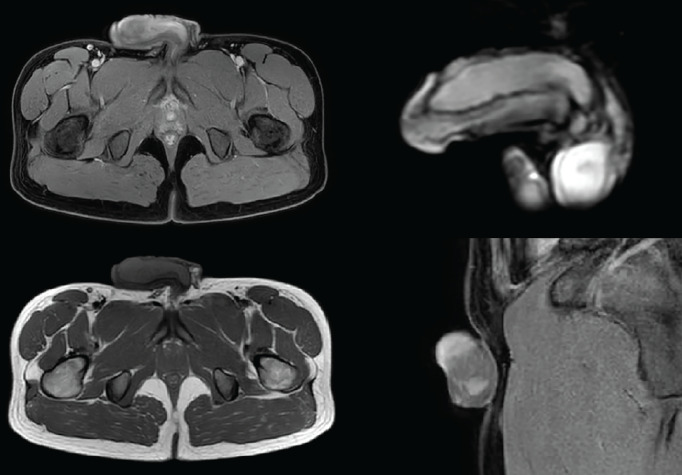

阴茎的恶性肿瘤并不常见,最常见的是鳞状细胞癌。非霍奇金淋巴瘤发生在一半的患者的结外部位,但在阴茎极为罕见。这里,一个24岁的阴茎肿块是非霍奇金淋巴瘤病例报告。体格检查和影像学检查发现阴茎左侧海绵体远端2厘米病变,并向海绵体近端延伸。在全身麻醉下从左侧海绵体远端切除活检。切除材料的组织病理学检查显示弥漫性大b细胞淋巴瘤伴生发后中心细胞表型。虽然它是罕见的患者表现为阴茎肿块,淋巴瘤累及的可能性应铭记在心。它可以模拟佩罗尼氏病或海绵体血栓形成。